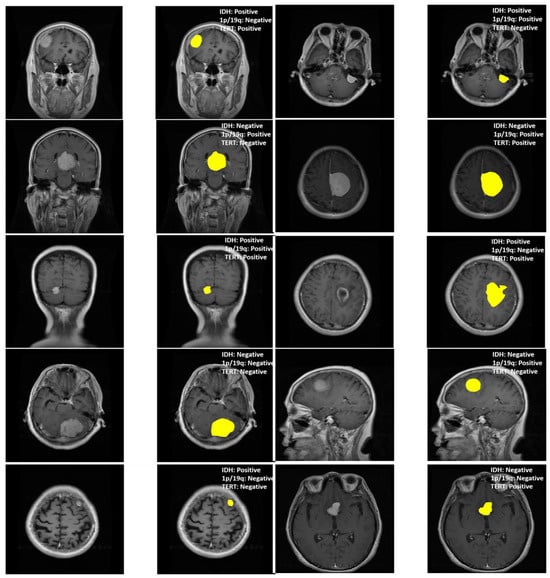

In this study, we also evaluated MGMT-Net’s ability to predict three clinically significant molecular markers: IDH mutation, 1p/19q co-deletion, and TERT promoter mutation, all of which were preoperatively inferred from multi-modal MRI scans. These molecular markers are central to glioma classification under the WHO CNS tumor grading system and play a critical role in patient prognosis, treatment planning, and therapeutic decision-making. The prediction task was formulated as a patient-level binary classification problem, with model outputs compared to ground truth labels obtained from histopathological analysis. On the unified TCGA-GBM/LGG and Erasmus Glioma Database (EGD) test cohort, MGMT-Net achieved AUC scores of 0.94 (IDH), 0.91 (1p/19q), and 0.90 (TERT), outperforming the best baseline model, which reached 0.92, 0.89, and 0.86, respectively. Corresponding classification accuracies were 92.4% for IDH, 88.9% for 1p/19q, and 86.7% for TERT. These results highlight not only MGMT-Net’s strong overall predictive performance but also its enhanced sensitivity to specific molecular markers when compared with leading 3D CNN and DenseNet-based approaches. This performance advantage is primarily attributed to the model’s attention-based global feature pooling strategy, which selectively emphasizes clinically informative regions within the volumetric MRI data during feature extraction Figure 3.

As an example, the model often focuses on the tumor core or ceases to focus on enhancing features when IDH status is being predicted. This focus overlaps with imaging features associated with the mutation. In the table below, these results are presented along with comparisons of MGMT-Net and the best-performing conventional deep learning baseline Table 2.

To gauge interpretability, we came up with Grad-CAM visualizations and attention heatmaps for typical cases stemming from biomarkers. As depicted in Figure 6, MGMT-Net kept on highlighting the tumor regions, which were of utmost biological relevance, during its prediction. In the case of IDH mutation, the most activated areas were around the non-enhancing tumor core; whereas for TERT prediction, the attention was at the enhancing rim and the necrotic boundary; and for 1p/19q co-deletion, the model was focused on the diffuse infiltrative margins seen in the FLAIR sequences.

The noted patterns correspond greatly with the radiogenomic associations that have been mentioned in previous studies and hence, they are an indication of the biological plausibility of MGMT-Net’s predictions. Furthermore, by looking at the CMAF weights, we found modality-specific attribution: FLAIR features were the most prominent in the peritumoral edema delineation, T1ce showed the vascular regions, and T2 was for the boundary sensitivity. Such findings, combined, lead to the conclusion that MGMT-Net is not only a predictor of accurate outcomes but also a provider of the interpretable cues that are consistent with neuro-oncological knowledge.